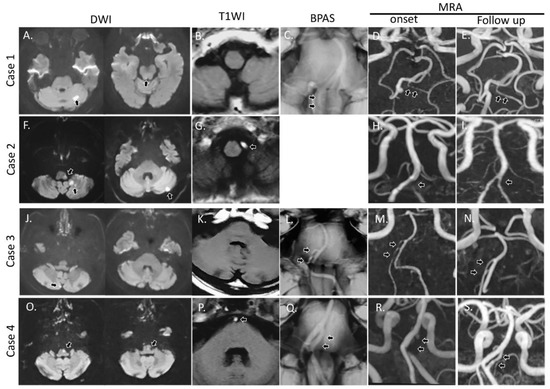

3.1. Case 1

3.2. Case 2

3.3. Case 3

3.4. Case 4